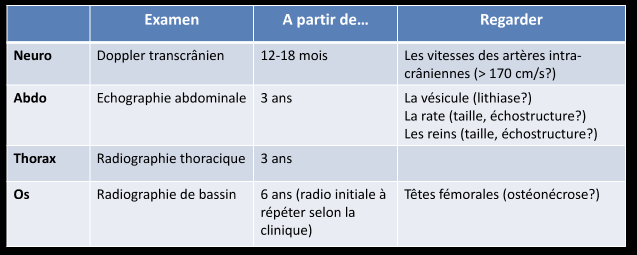

Dépistage annuel

Cerveau

- AVCs ischémiques (200x risque)

- Troubles perfusionnels ++

- Sténoses vasculaires

- Territoires jonctionnels (Carotide++)

- Rarement Thrombo-emboliques

!

!

- Moya-Moyas

- Anévrismes

Thorax

- Pneumonies très fréquentes

- (100x plus sensibles aux infections)

- Peuvent faire des fibroses à long terme

- Acute Chest Syndrome: Infarctus pulmonaires (vaso-occlusif, parfois embols graisseux)

- Graves

- Condensations pulmonaires

- Touchant au moins un segment

- Difficile à distinguer d’une infection

Ostéo-articulaire

- Peristance de moelle rouge dans les os longs

- Elargissement de la diploe (Aspect moucheté)

- Crises vaso-occlusives (Infarctus osseux, souvent multiples, l’hypersignal T1 spontané est spécifique pour le DD avec ostéomyélite)

- Ostéomyélites (DD de l’infarctus, pas évident, a suspecter si il ya des abcès, collections)

- Déformation en H des vertèbres (infarctus du centre du plateau)

Hépatique

- Surcharge en Fer (dues aux transfusions répetées)

Vésicule biliaire

- Lithiases (fréquentes)

Rate

- Infarctus à répétition → Asplénie fonctionelle

- Splénomégalies

- Rates atrophiques et calcifiées (à long terme) = auto-splénectomie

- Syndrome de Séquestration splénique = Splénomégalie qui séquestre +++ le volume sanguin = Choc hypovolémique !

Reins

- Infarctus Rénaux dans la médullaire

- Dedifférenciation cortico médullaire à l’US

- Risque de Carcinome Medullaire (tumeur rare presque exclusivement trouvée chez les Drepa)